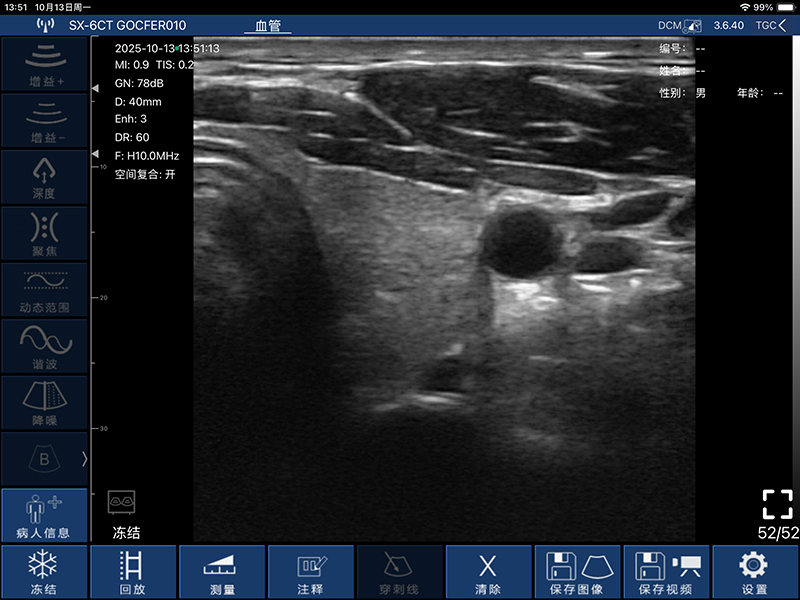

• 深度:凸阵探头90/160/220/305mm,线阵探头20/40/60/80mm,相控阵探头90/120/140/160MM

• 显示模式:B、B/M、Color、PDI、PW

• 图像调整:增益、动态范围、焦点、深度、谐波、降噪

• 穿刺辅助功能:平面内穿刺引导功能、平面外穿刺引导线功能、

血管自动测量功能